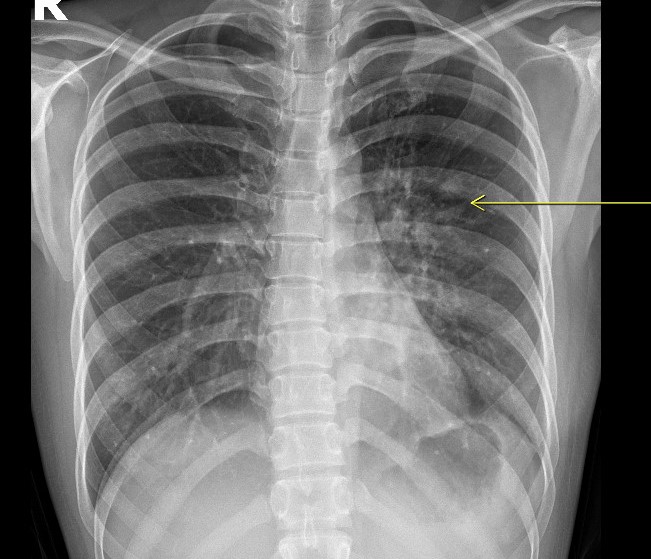

Khi thăm khám tại Hồng Ngọc, bệnh nhân sẽ được chỉ định thực hiện các xét nghiệm cần thiết như xét nghiệm máu, chụp X-quang phổi, khám tai mũi họng và nội soi phế quản (nếu cần) để đánh giá tình trạng bệnh.